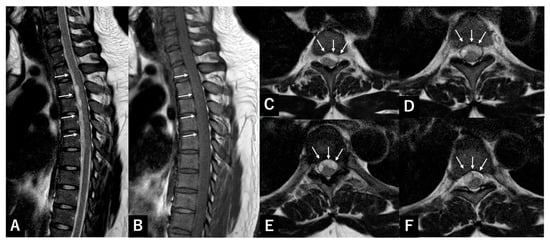

Open AccessArticle

Shun Okuwaki, Hiroshi Takahashi, Katsuya Nagashima, Tomoyuki Asada, Takane Nakagawa, Takahiro Sunami, Yosuke Ogata, Kotaro Sakashita, Hisanori Gamada, Kousei Miura, Hiroshi Noguchi, Yosuke Takeuchi, Toru Funayama, Masao Koda and Masaki Tatsumura

Abstract

Background/Objectives: Spontaneous spinal subdural hematoma (SSSDH) is a rare and severe condition that causes rapid neurological decline. Spontaneous spinal epidural hematoma (SSEH) presents similarly but is more common, and surgical management differs because SSSDH requires an intradural approach. Few studies have assessed the reliability of magnetic resonance imaging (MRI) features used to distinguish SSSDH from SSEH in patients requiring surgery. Methods: We retrospectively reviewed 27 patients who underwent surgical evacuation of spinal hematomas at two institutions (2015–2025). Definitive hematoma location was determined intraoperatively. Four MRI features—shape (crescentic vs. biconvex), location (ventral vs. dorsal), craniocaudal length (<5 vs. ≥5 segments), and spinal region—were independently evaluated by two reviewers. Inter- and intra-rater reliability was assessed using agreement rate and Cohen’s kappa (κ) with 95% confidence intervals (95% CIs). Results: Among 27 cases, three (11.1%) were SSSDH and 24 were SSEH. Hematoma location, length, and spinal region demonstrated perfect inter- and intra-rater agreement (κ = 1.00). For hematoma shape, intra-rater agreement was good (96.2%, κ = 0.84; 95% CI 0.52–1.00), whereas inter-rater agreement was poor to fair (84.6%, κ = 0.26; 95% CI −0.25–0.77). Notably, two of the three SSSDHs demonstrated a biconvex configuration, and 83.3% of SSEHs also exhibited a biconvex morphology. Conclusions: MRI features such as hematoma location, extent, and spinal level were highly reproducible, whereas hematoma shape showed limited reliability. Although ventral hematomas most strongly suggest SSSDH, atypical SSEH presentations occur. When dorsal exposure reveals no epidural hematoma, intradural exploration should be promptly considered.